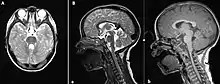

The disorder is characterized by absence or underdevelopment of the cerebellar vermis and a malformed brain stem (molar tooth sign), both of which can be visualized on a transverse view of head MRI scan.[17] Together with this sign, the diagnosis is based on the physical symptoms and genetic testing for mutations. If the gene mutations have been identified in a family member, prenatal or carrier diagnosis can be pursued.[4]